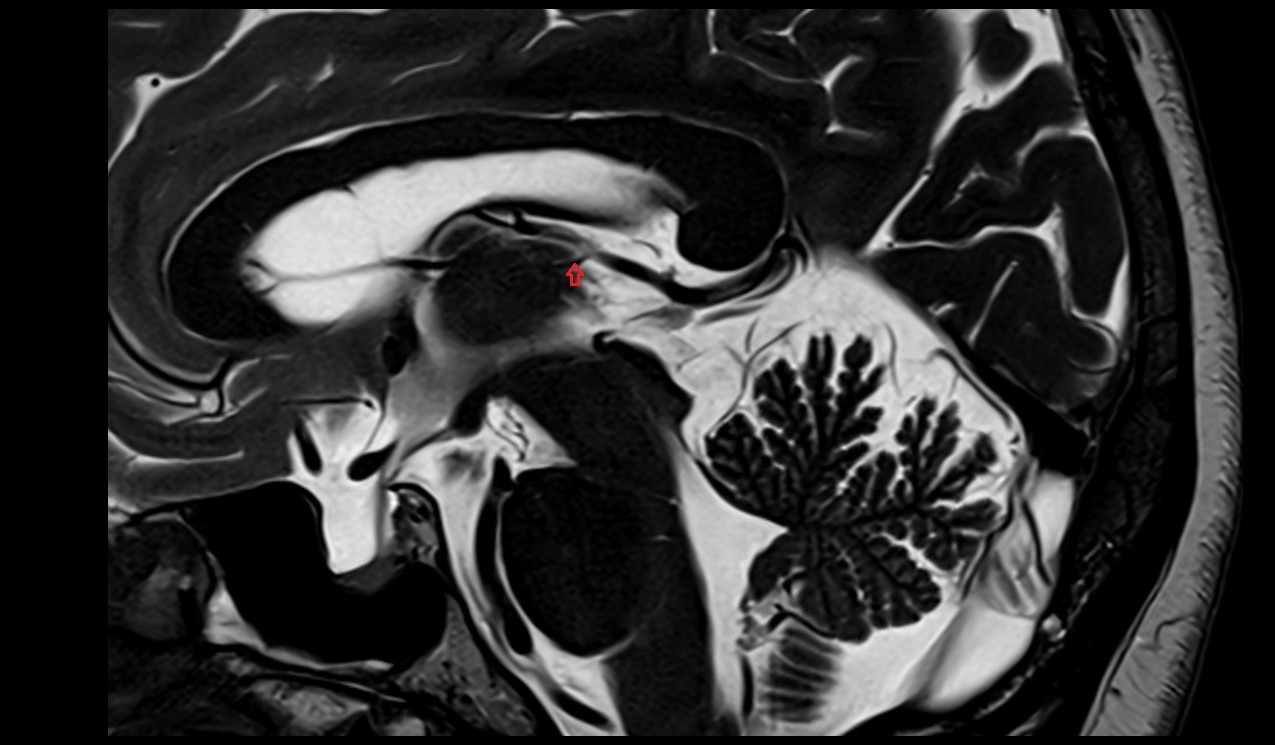

- Fetal brain

- Fetal caudate nucleus

- Fetal thalamus

- Fetal pons

- Fetal cerebellum

- Fetal third ventricle

- Fetal fourth ventricle

- Fetal lateral ventricle